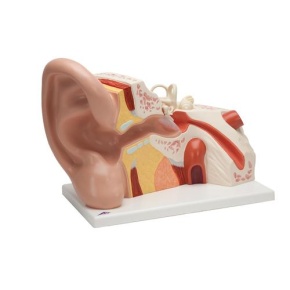

Schreibtischmodell des Ohrs, 1,5-fache Größe

Schreibtischmodell des Ohrs, 1,5-fache Größe